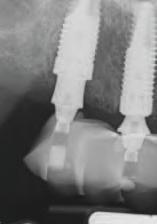

INSERAREA IMPLANTURILOR

Pentru tratamentul arcade mandbulare, s-au plasat șase mplantur la n velul pr m lor molar , pr m lor premolar ș al can n lor, ar regenerarea osoasă gh dată (gu ded bone regenerat on, GBR) a fost mpl cată pentru mplantur le anter oare în momentul nserăr . S-a obț nut

La arcada max lară, procedura a debutat cu îndepărtarea m n - mplantur lor ex stente, f nd pos b lă afrontarea țesutur lor mo . S-a utl zat un gh d ch rurg cal suportat de țesut moale pentru or entarea freze p lot, ar mplantur le posteroare angulate au fost alese pentru a ev ta s nusur le pneumat zate. S-au nserat șase mplantur cu o d strbuț e antero-poster oară adecvată, obț nându-se o bună stab l tate pr mară. Restaurarea prov zor e med ată a fost convert tă într-o restaurare f xă prov zor e suportată de mplantur pe baza setăr restaurator n ț ale.

S-a stab l t că este necesar un des gn FP1 al proteze pentru mandbulă, în t mp ce un des gn FP3 se mpunea în cazul max larulu . S-a efectuat o tehn că duală de scanare pentru a captura o mag ne 3D a creste restante folos nd marker

10. Ghidul chirurgical mandibular a fost creat pentru a fi susținut de mini-implanturile existente.

11. La mandibulă, implanturile au fost plasate fără a interfera cu mini-implanturile existente.